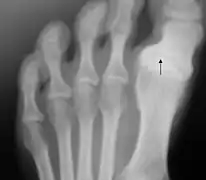

Hallux varus

L'hallux varus est une déformation de l'articulation du gros orteil.

Cette déformation inhabituelle peut être congénitale ou acquise à la suite d'un traumatisme. Prise tôt, une réduction manuelle est possible, par le port de semelles par exemple. Sinon, selon l'avancement, le degré de déformation et le niveau d'arthrose, on pourra déplacer le tendon ou faire une arthrodèse.

Elle peut aussi survenir de façon exceptionnelle et imprévisible après une opération de l'hallux valgus dans laquelle la correction de l'alignement du gros orteil a été exagérée.